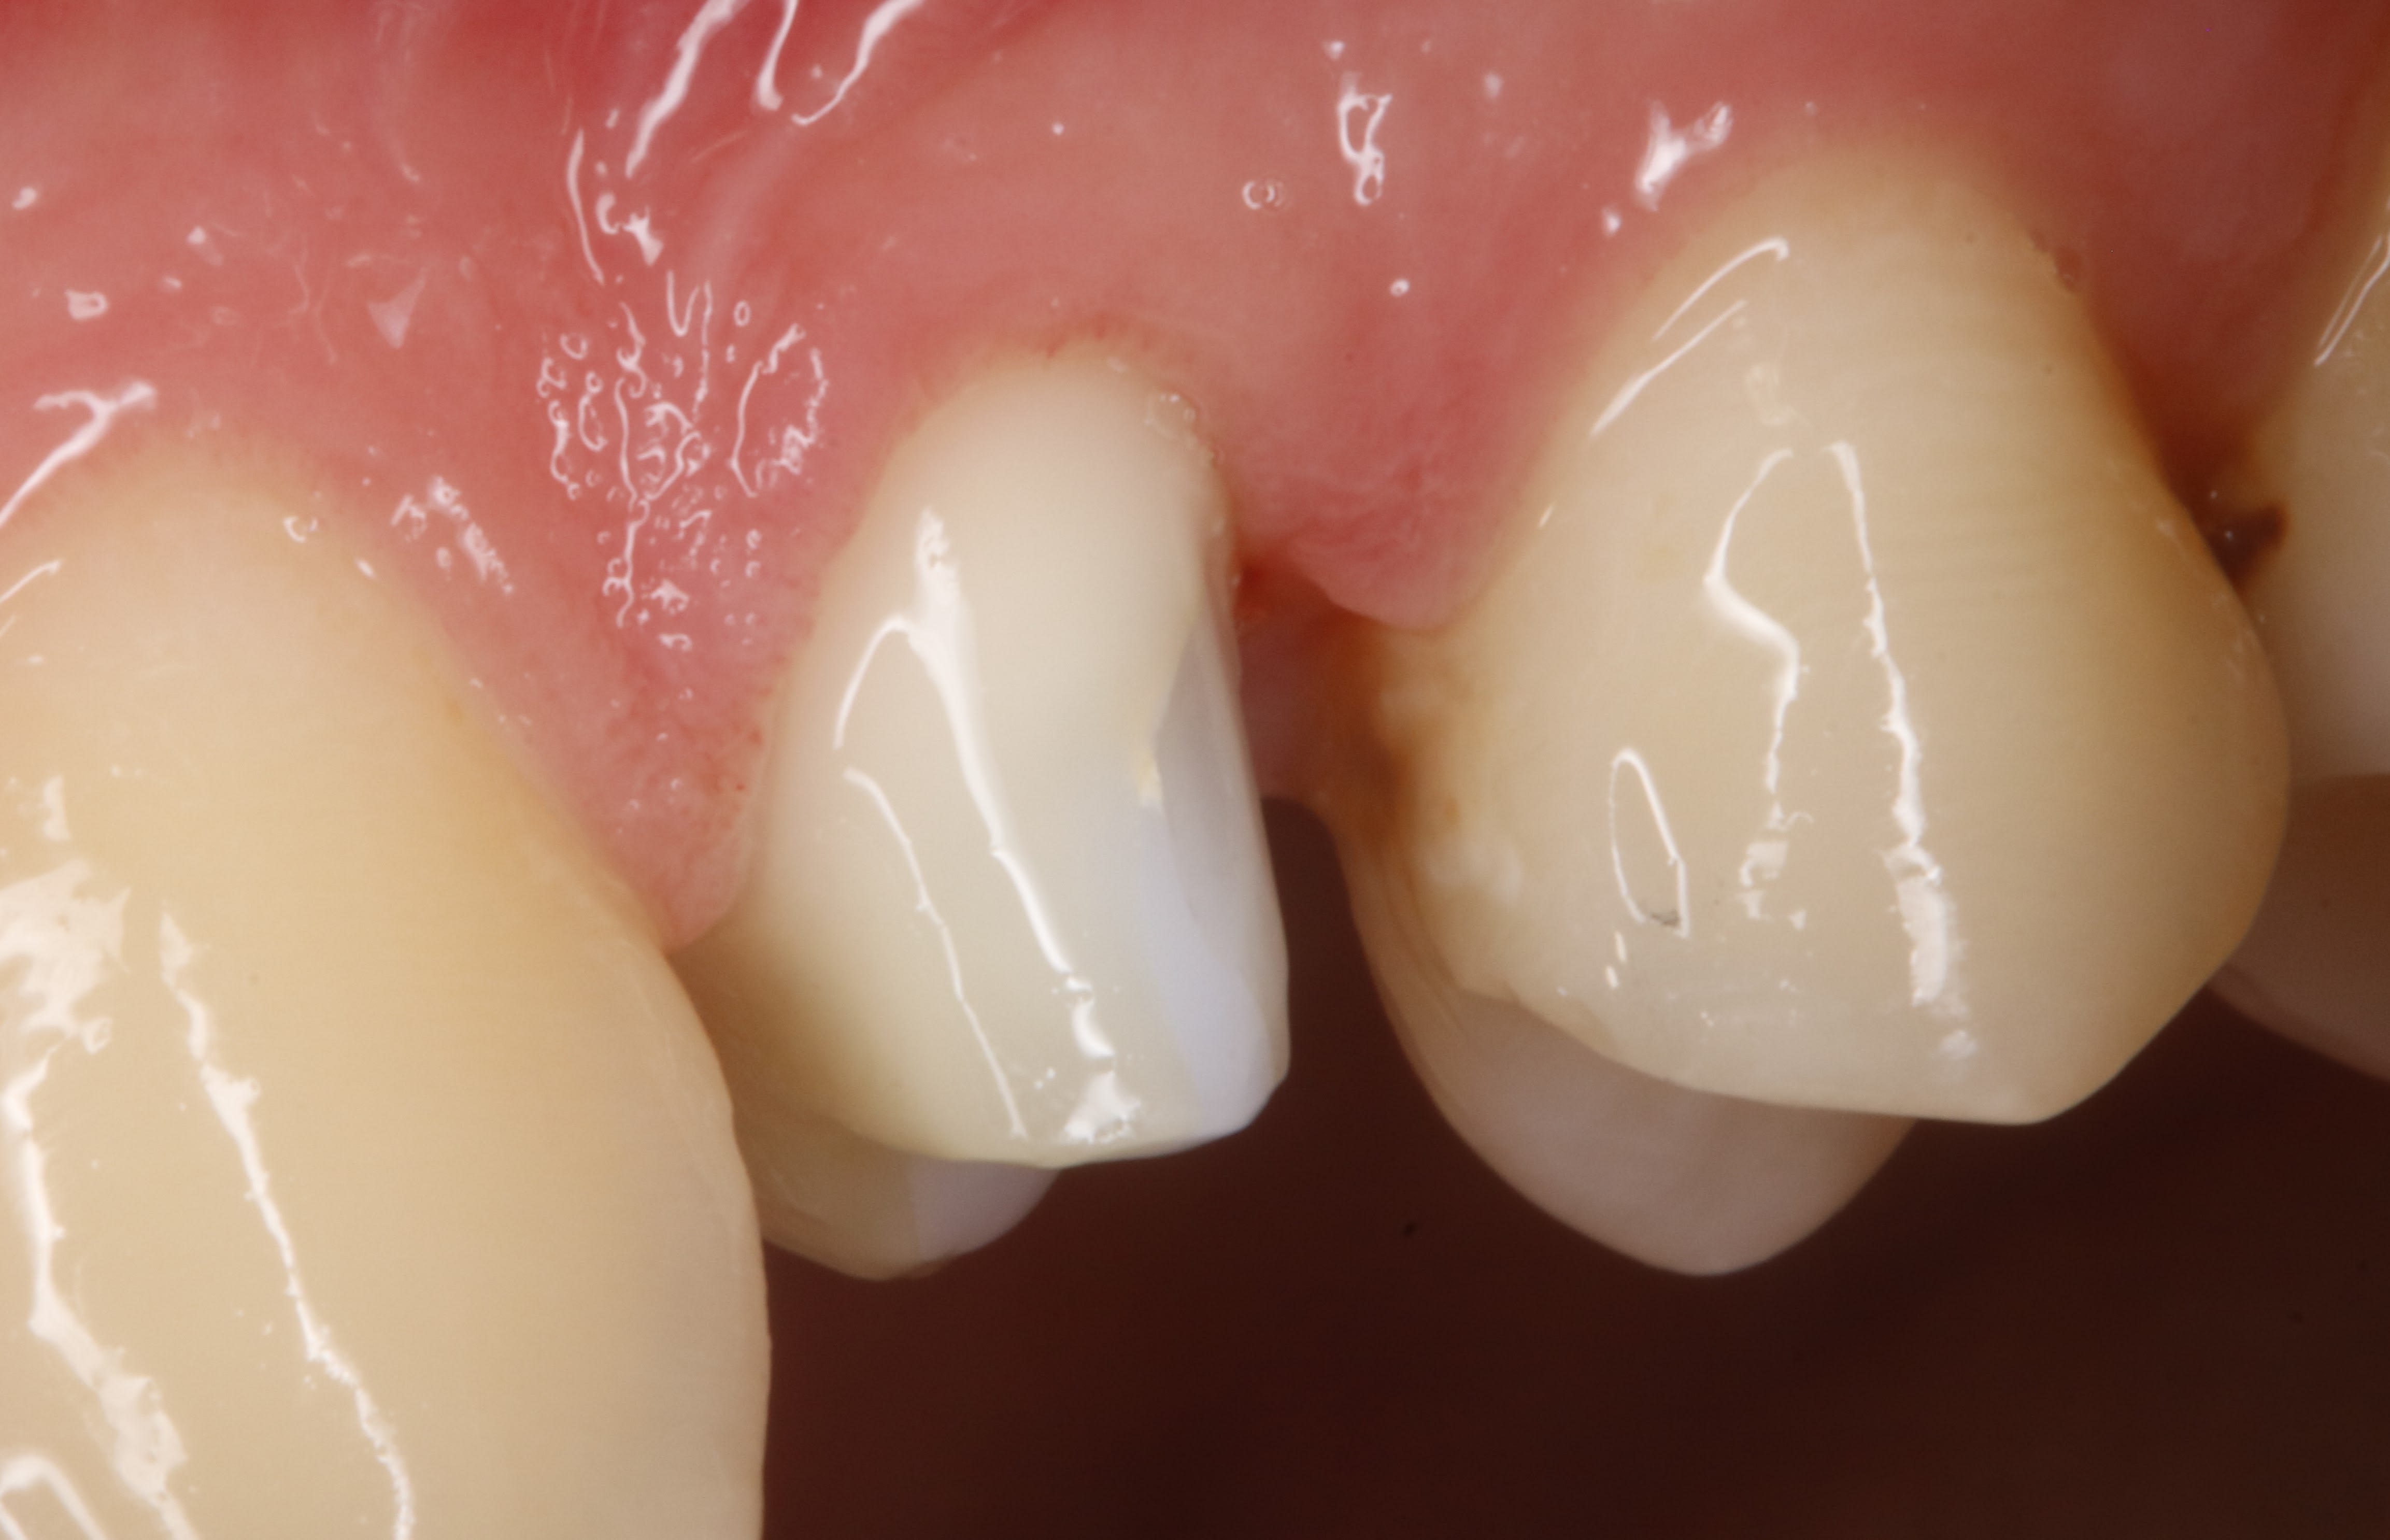

et le plus simple était de couper la papille emboucanée et là on est à 3 semaines sans prov , aujourd'hui c est le jour de la pose .

N5mjmu4g20ggfbuktclhfzb4i0it - Eugenol

3os0pxsfpntwg491bfybvwlatt1p - Eugenol

29/04/2025 à 11h39

un avantage de ne pas mettre de prov , c est qu' on ne t appellera jamais pour le resceller :-))

mais au delà de ça cela ta permet de faire ton curetage rotatif avant la finition de la taille .

la taille , le jour du curetage ( donc de la 1 ere séance) les limites sont tjs juxta voir sans limites du tout au niveau proximal .

et l autre avantage , c est que le jour de l empreinte , il t est très facile de repréciser les limites infra sans aucune goute de sang .

la photo de ce matin , c est le jour de l empreinte limites retaillées .